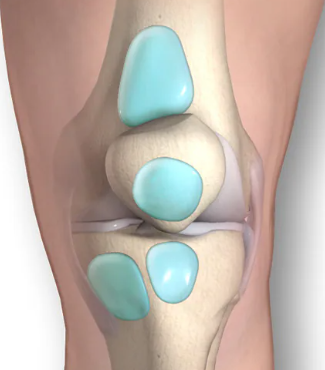

무릎 관절의 삼출액은 무릎 관절 내에 활막에서 분비되는 체액이 정상보다 과도하게 쌓여 발생하는 상태를 말하며, 흔히 "무릎에 물이 찼다" 또는 "무릎 부종"으로 표현됩니다. 활막은 관절낭을 덮고 관절을 원활하게 움직이게 하는 윤활액을 만드는 조직인데, 염증이나 부상 등으로 인해 이 활막에서 과도하게 체액이 생성되면서 무릎이 붓고 통증, 뻣뻣함, 운동 범위 제한 등의 증상이 나타납니다.

퇴행성 관절염(골관절염): 연골 손상과 염증으로 인해 무릎 관절 내에 체액이 축적됩니다.

활액낭염(점액낭염): 무릎의 윤활막 주머니인 활액낭의 염증이 체액 증가는 원인 중 하나입니다.